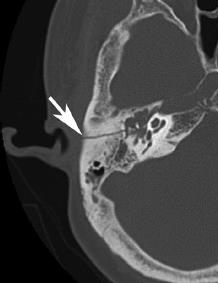

Temporal Bone Fractures

Motor Cycle Accident Victims

Two victims of motor cycle accidents were brought to the ER. After stabilization, both were sent for CT scans. Temporal Bone Fractures

Findings in CT Scans

- A: Transverse Fracture.

- B: Longitudinal Fracture.